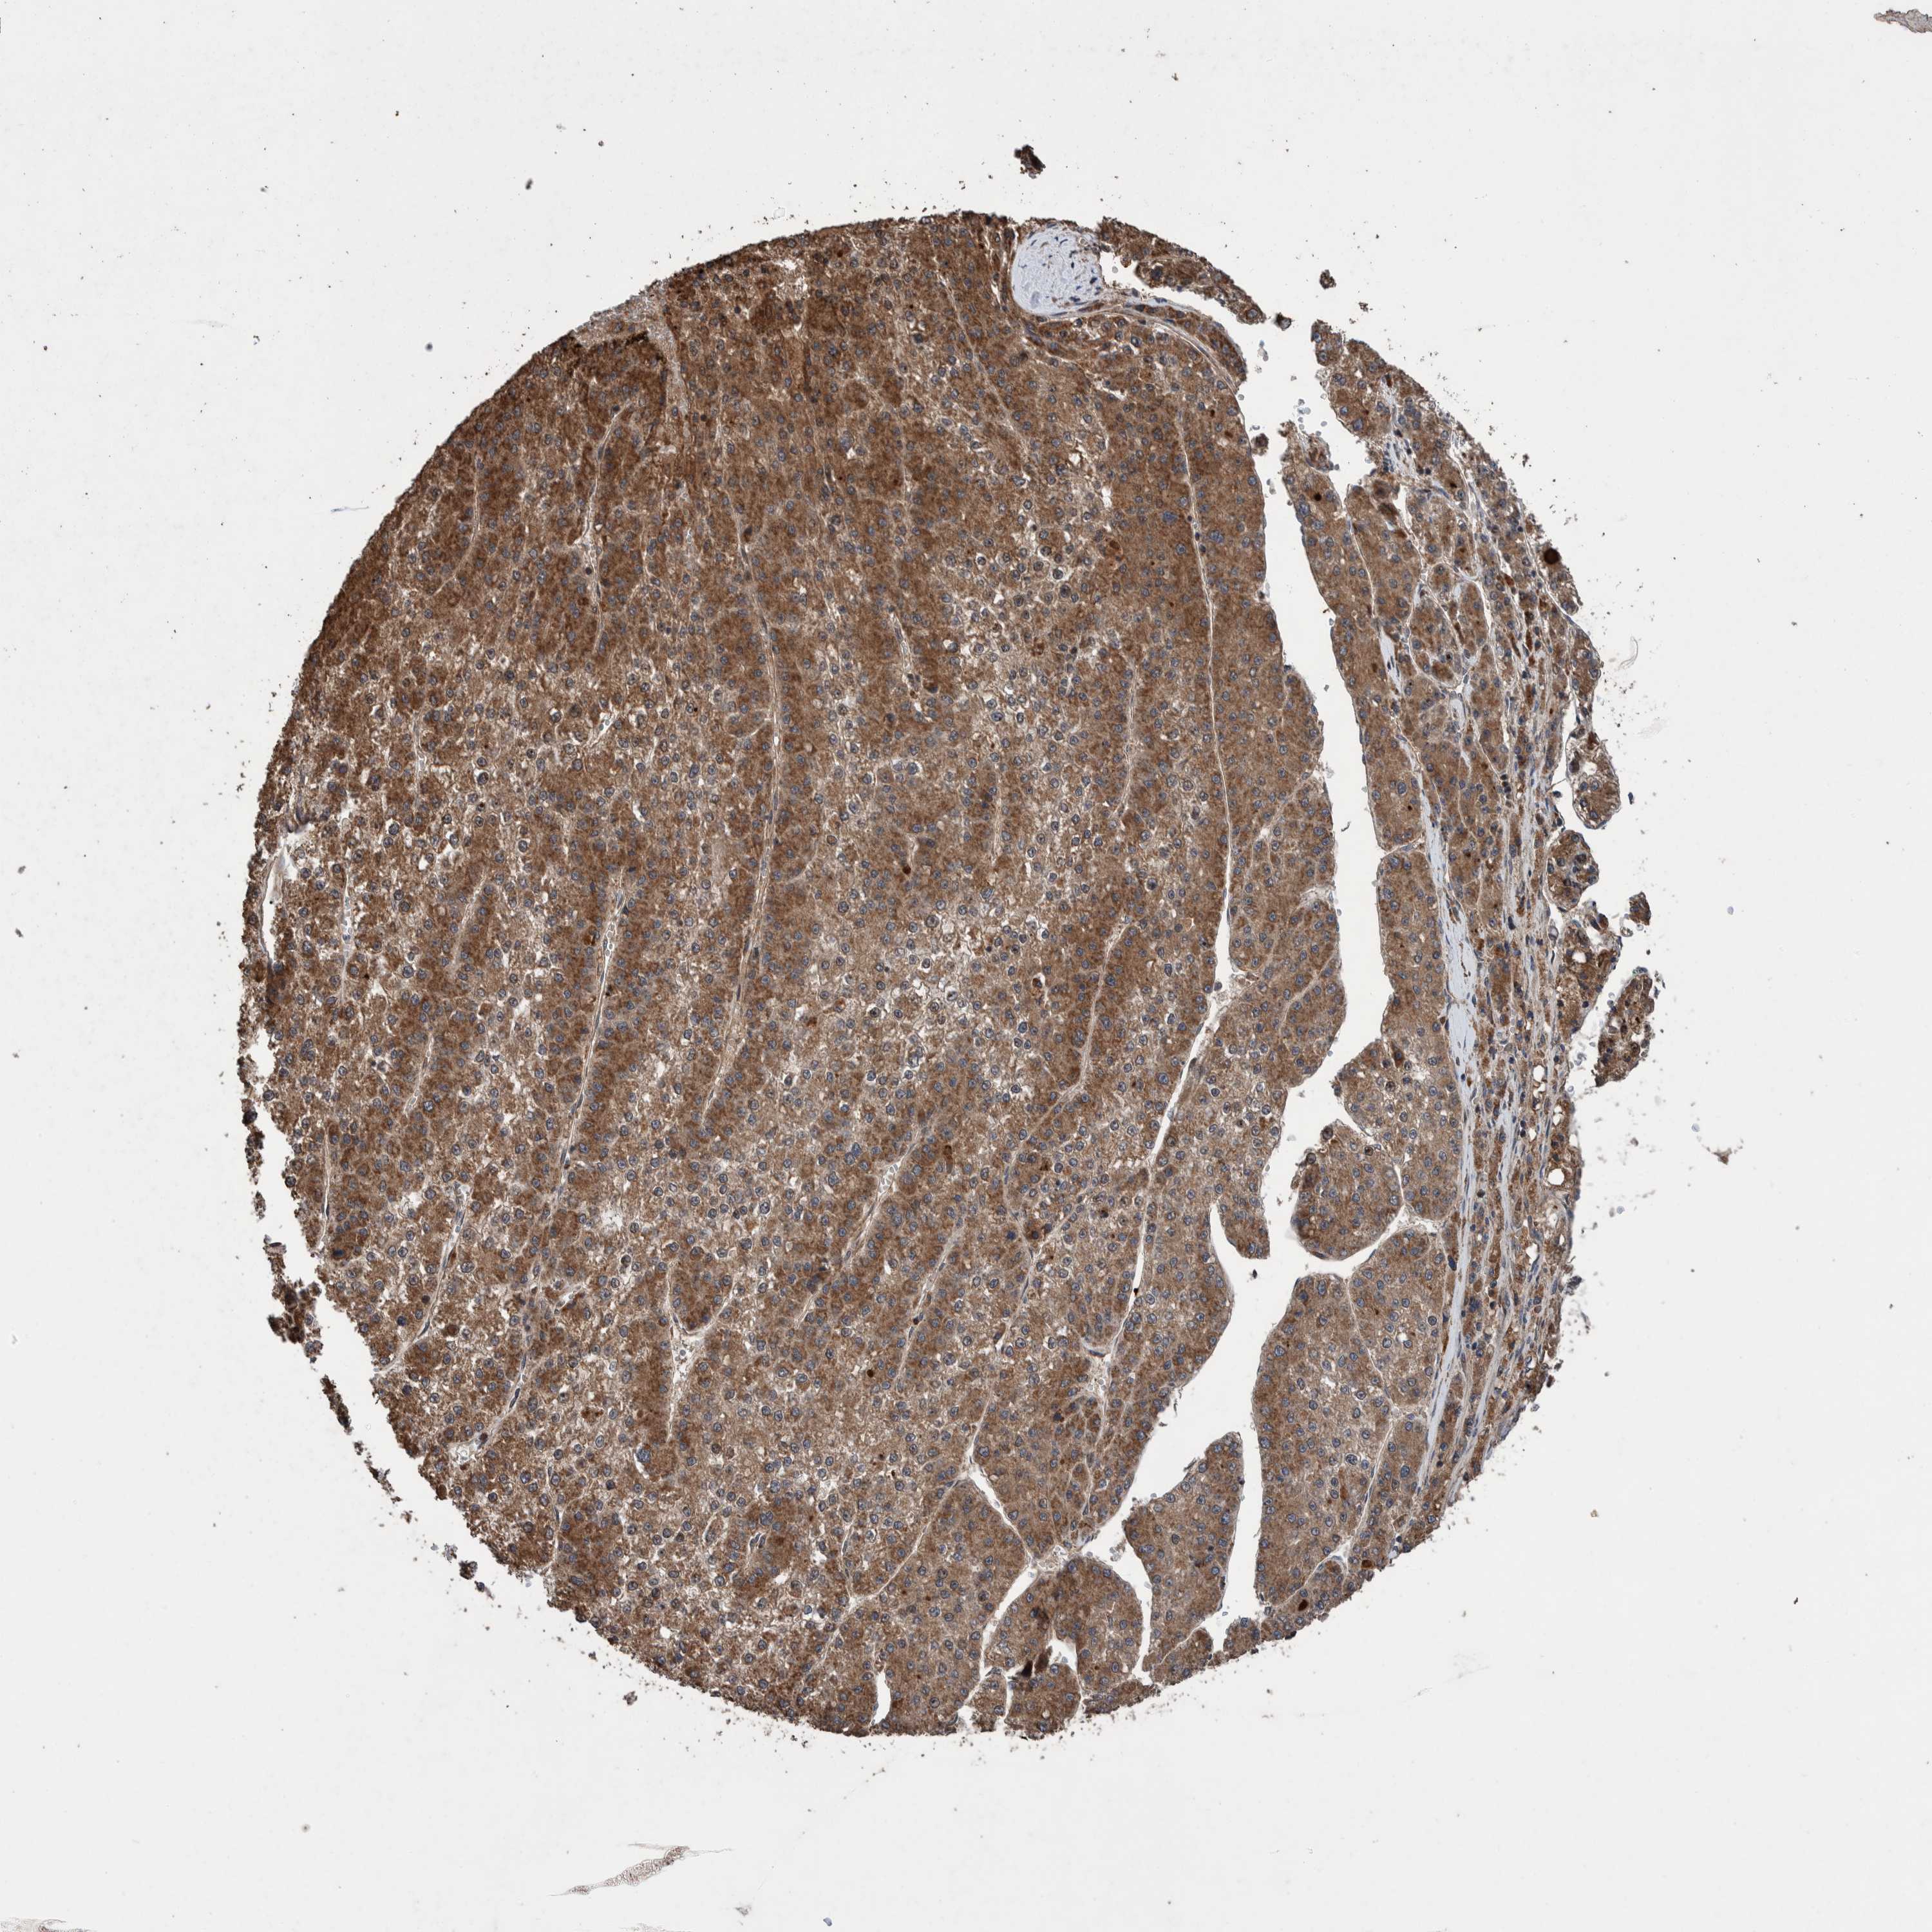

LIVER CANCER - Protein expressioni

A mouse-over function shows sample information and annotation data. Click on an image to view it in a full screen mode. Samples can be filtered based on level of antibody staining by selecting one or several of the following categories: high, medium, low and not detected. The assay and annotation is described here.

Note that samples used for immunohistochemistry by the Human Protein Atlas do not correspond to samples in the TCGA dataset.

Antibody stainingi

Antibody staining in the annotated cell types in the current human tissue is reported as not detected, low, medium, or high, based on conventional immunohistochemistry profiling in selected tissues. This score is based on the combination of the staining intensity and fraction of stained cells.

Each image is clickable and will lead to virtual microscopy that enables deeper exploration of all samples and also displays staining intensity scores, fraction scores and subcellular localization as well as patient and tissue information for each sample.

Antibody HPA023623

Antibody HPA066431

Staining

High

Medium

Low

Not detected

Intensity

Strong

Moderate

Weak

Negative

Quantity

>75%

75%-25%

<25%

None

Location

Nuclear

Cytoplasmic/membranous

Cytoplasmic/membranous,nuclear

Cholangiocarcinoma

Carcinoma, Hepatocellular, NOS